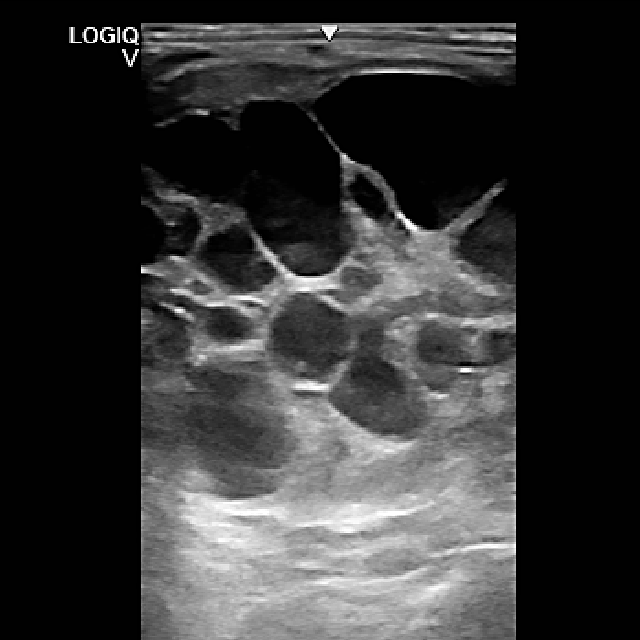

- Wenn eine vermehrte Füllung der Sehnenscheide („Galle“), z.B. im Bereich des Fesselkopfes, zur Entstehung einer Lahmheit beiträgt, führen wir eine sorgfältige Untersuchung mittels Ultraschall und Kontrastradiographie durch. Häufig ergeben sich dann bereits Hinweise auf einen Sehnenschaden innerhalb der Sehnenscheide.

- Im Rahmen einer minimalinvasiven Sehnenscheidenspiegelung (Tendovaginoskopie) wird der Schaden dann unter Sichtkontrolle geglättet und aufgefaserte Sehnenanteile werden entfernt, damit die Sehnenscheidenentzündung abklingen kann.

- Tumore am Eierstock (Ovar) können z. B. ein aggressives Verhalten der Stute oder Rittigkeitsprobleme auslösen. Nach einer umfassenden Untersuchung (u.a. Ultraschall, Hormonprofil) kann die Diagnose gestellt werden.

- Der häufigste Tumor ist der Granulosazelltumor. Nach der chirurgischen Entfernung ist die Prognose sehr gut. Die Operation wird in unserer Klinik minimal invasiv am stehenden Patienten durchgeführt.